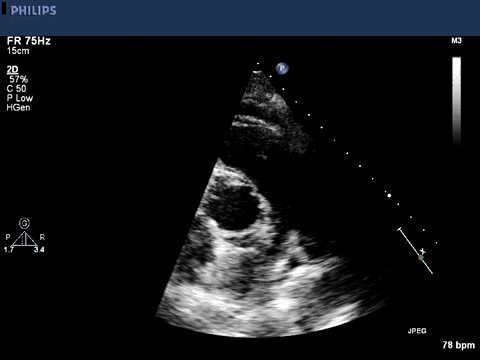

Given her history of endocarditis, an echocardiogram was performed.